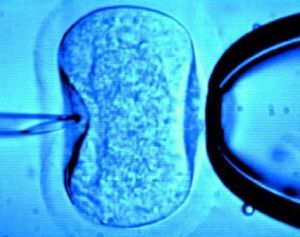

體外受精,是指採用一種特殊的方法,從婦女體內將卵子取出,置入試管或器皿內,同時也將精子置於該試管或器皿中,讓其精子與卵子受精,受精卵在培養箱中培育約72小時後成為胚胎,再將胚胎移植到子宮中,讓其在子宮中著床、發育直至分娩。由於這一過程是在體外受精並從體外將胚胎移植至子宮中,所以這一技術又稱為體外受精與胚胎移植技術,也稱試管嬰兒技術。

試管嬰兒的意思,是從精子庫或某男士身上取出精子,與某女子的卵子在試管內配合,成為胚胎後,又植回該女士體內。實際上試管嬰兒也分多類,絕大部分人能接受的,是將丈夫的精子與妻子的卵子在試管內配合成胚胎後,再植回妻子體內繼續受孕。這種做法在道德上沒有問題,只不過是利用先進的醫學科技幫他們夫婦一把罷了。